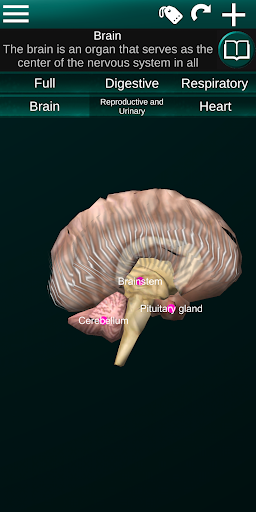

Internal Organs in 3D Anatomy لـ Vodafone Smart N9 Lite

(الأجهزة الداخلية في)

Internal Organs 3D Anatomy 3.4

يمكنك هنا تنزيل ملف حزمة تطبيق أندرويد "Internal Organs 3D Anatomy" الخاصة بجهازVodafone Smart N9 Lite مجانًا، نسخة ملف حزمة تطبيق أندرويد - 3.4 للتحميل على Vodafone Smart N9 Lite اضغط ببساطة على هذا الزر. إنه سهل وآمن. نحن نقدم فقط ملفات حزمة تطبيق أندرويد الأصلية. إذا انتهكت أية مواد موجودة في الموقع حقوقك قم بإبلاغنا من خلال